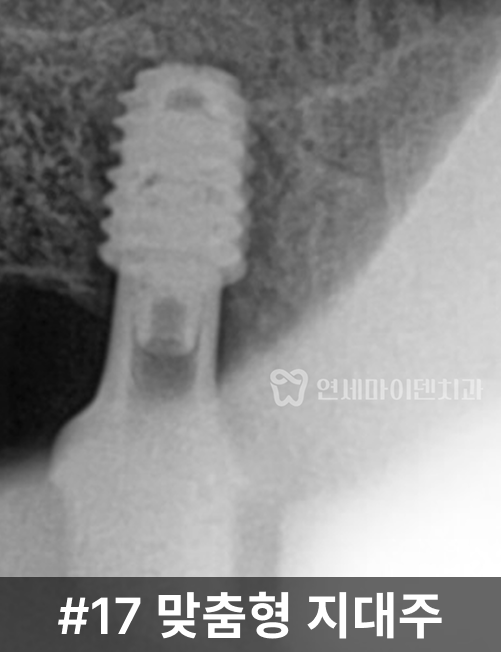

2차 수술을 진행했습니다.이후 맞춤형 지대주를 연결하고

최종 보철물을 제작해

저작 기능을 회복했습니다.치료 결과와 경과

치료 후 CT와 임상 사진에서

임플란트의 안정적인 고정 상태와

교합 회복을 확인할 수 있었습니다.앞쪽 16번 치아는

2년 이상 안정적으로 유지되고 있으며,뒤쪽 17번 임플란트 역시

상악동염 재발 없이